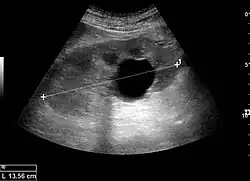

Простая почечная киста

Простая почечная киста — киста первого типа по классификации, предложенной американским радиологом Мортоном А. Босняком в 1986 году[1]. Это доброкачественная простая киста с тонкой стенкой без перегородок, кальцификаций или твёрдых компонентов. Имеет плотность видимости 0–20 единиц[2] по шкале Хаунсфилда, что примерно равно плотности воды. Для определения кисты достаточно компьютерной томографии без внутривенного контрастного вещества на основе гадолиния. В случаях когда гадолиний вводится, простая киста 1-й категории не должна демонстрировать значительного усиления становясь ярче не более чем на 10 единиц Хаунсфильда.

Простые почечные кисты тонкие, круглые мешочки заполнены прозрачной жидкостью, и они не являются злокачественными.